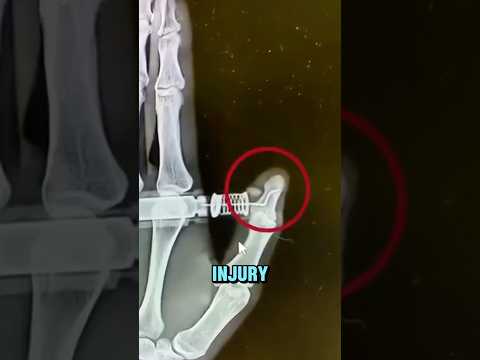

When an EpiPen Goes Wrong

EpiPen Gone Wrong ⚠️

Doctor Reacts: EpiPen fail

EpiPen Gone Wrong 😨

The EpiPen Mistake That Sent Her to the ER! 🚑💉⚠️